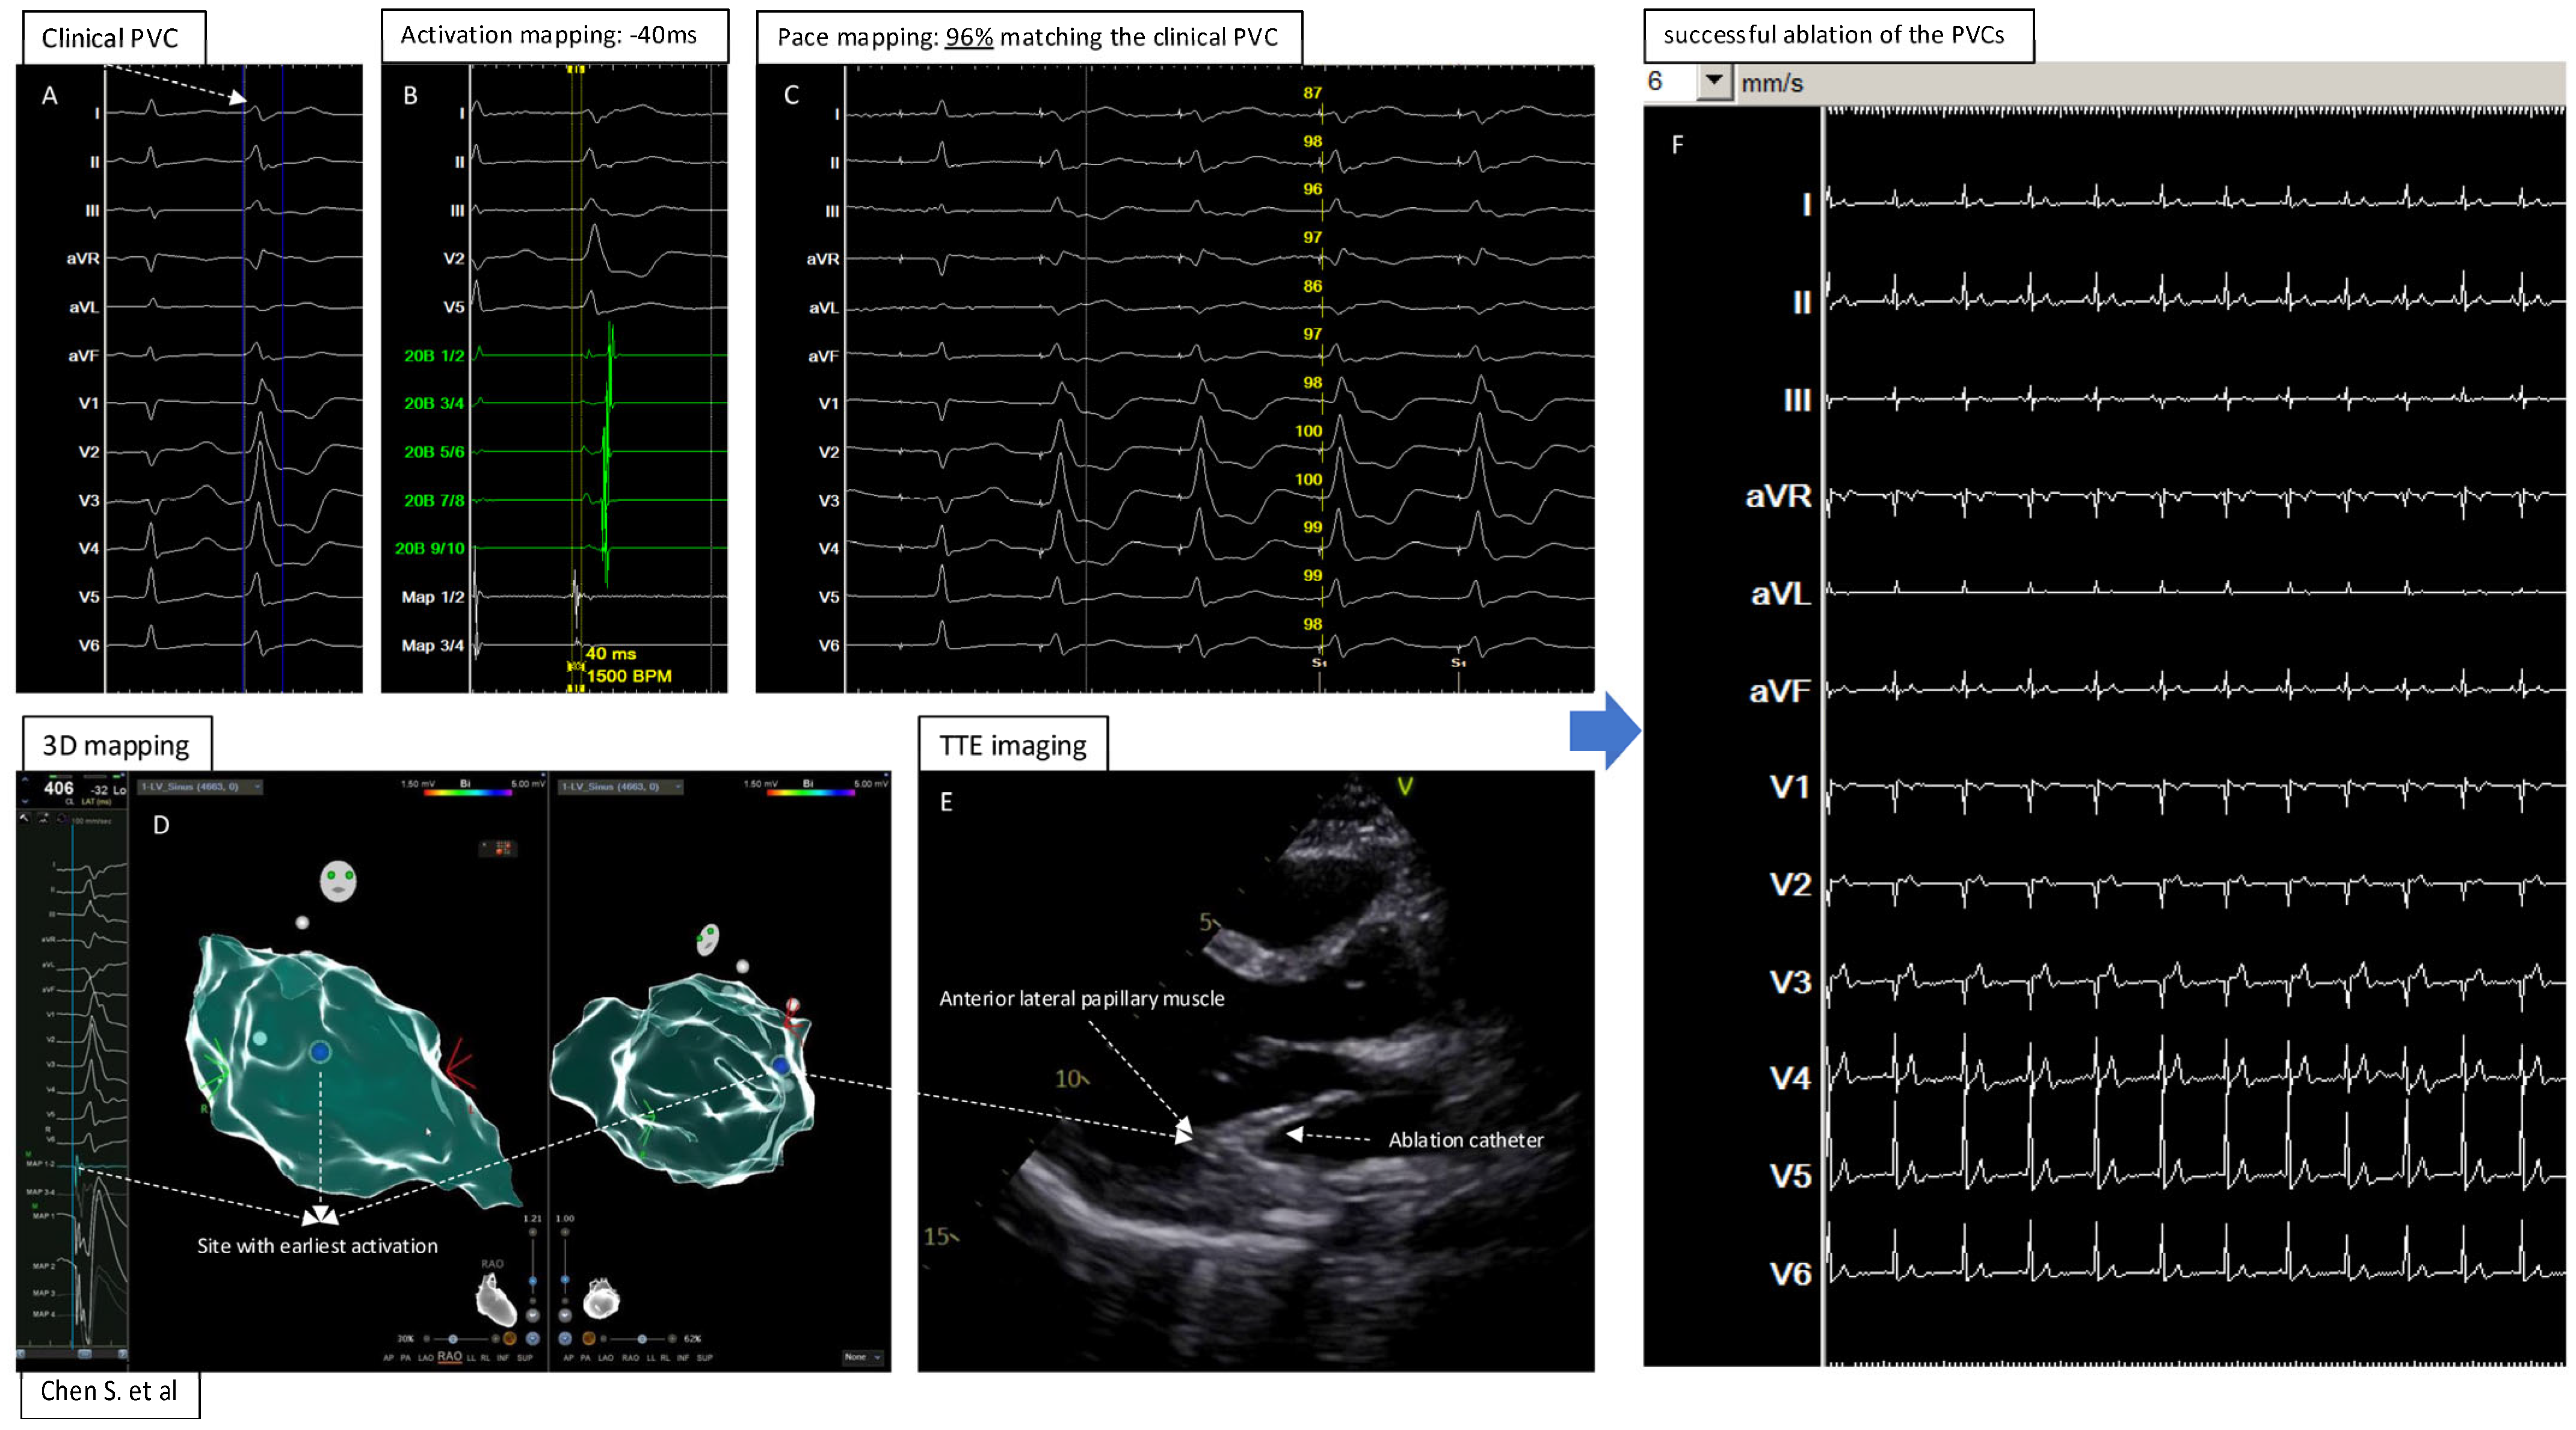

3D Map Combined with Transthoracic Echocardiography for Ablation of Premature Ventricular Contractions/Ventricular Arrhythmia from Papillary Muscle: A Technical Report

2. Methods and Results

Mapping and Ablation of the PVCs